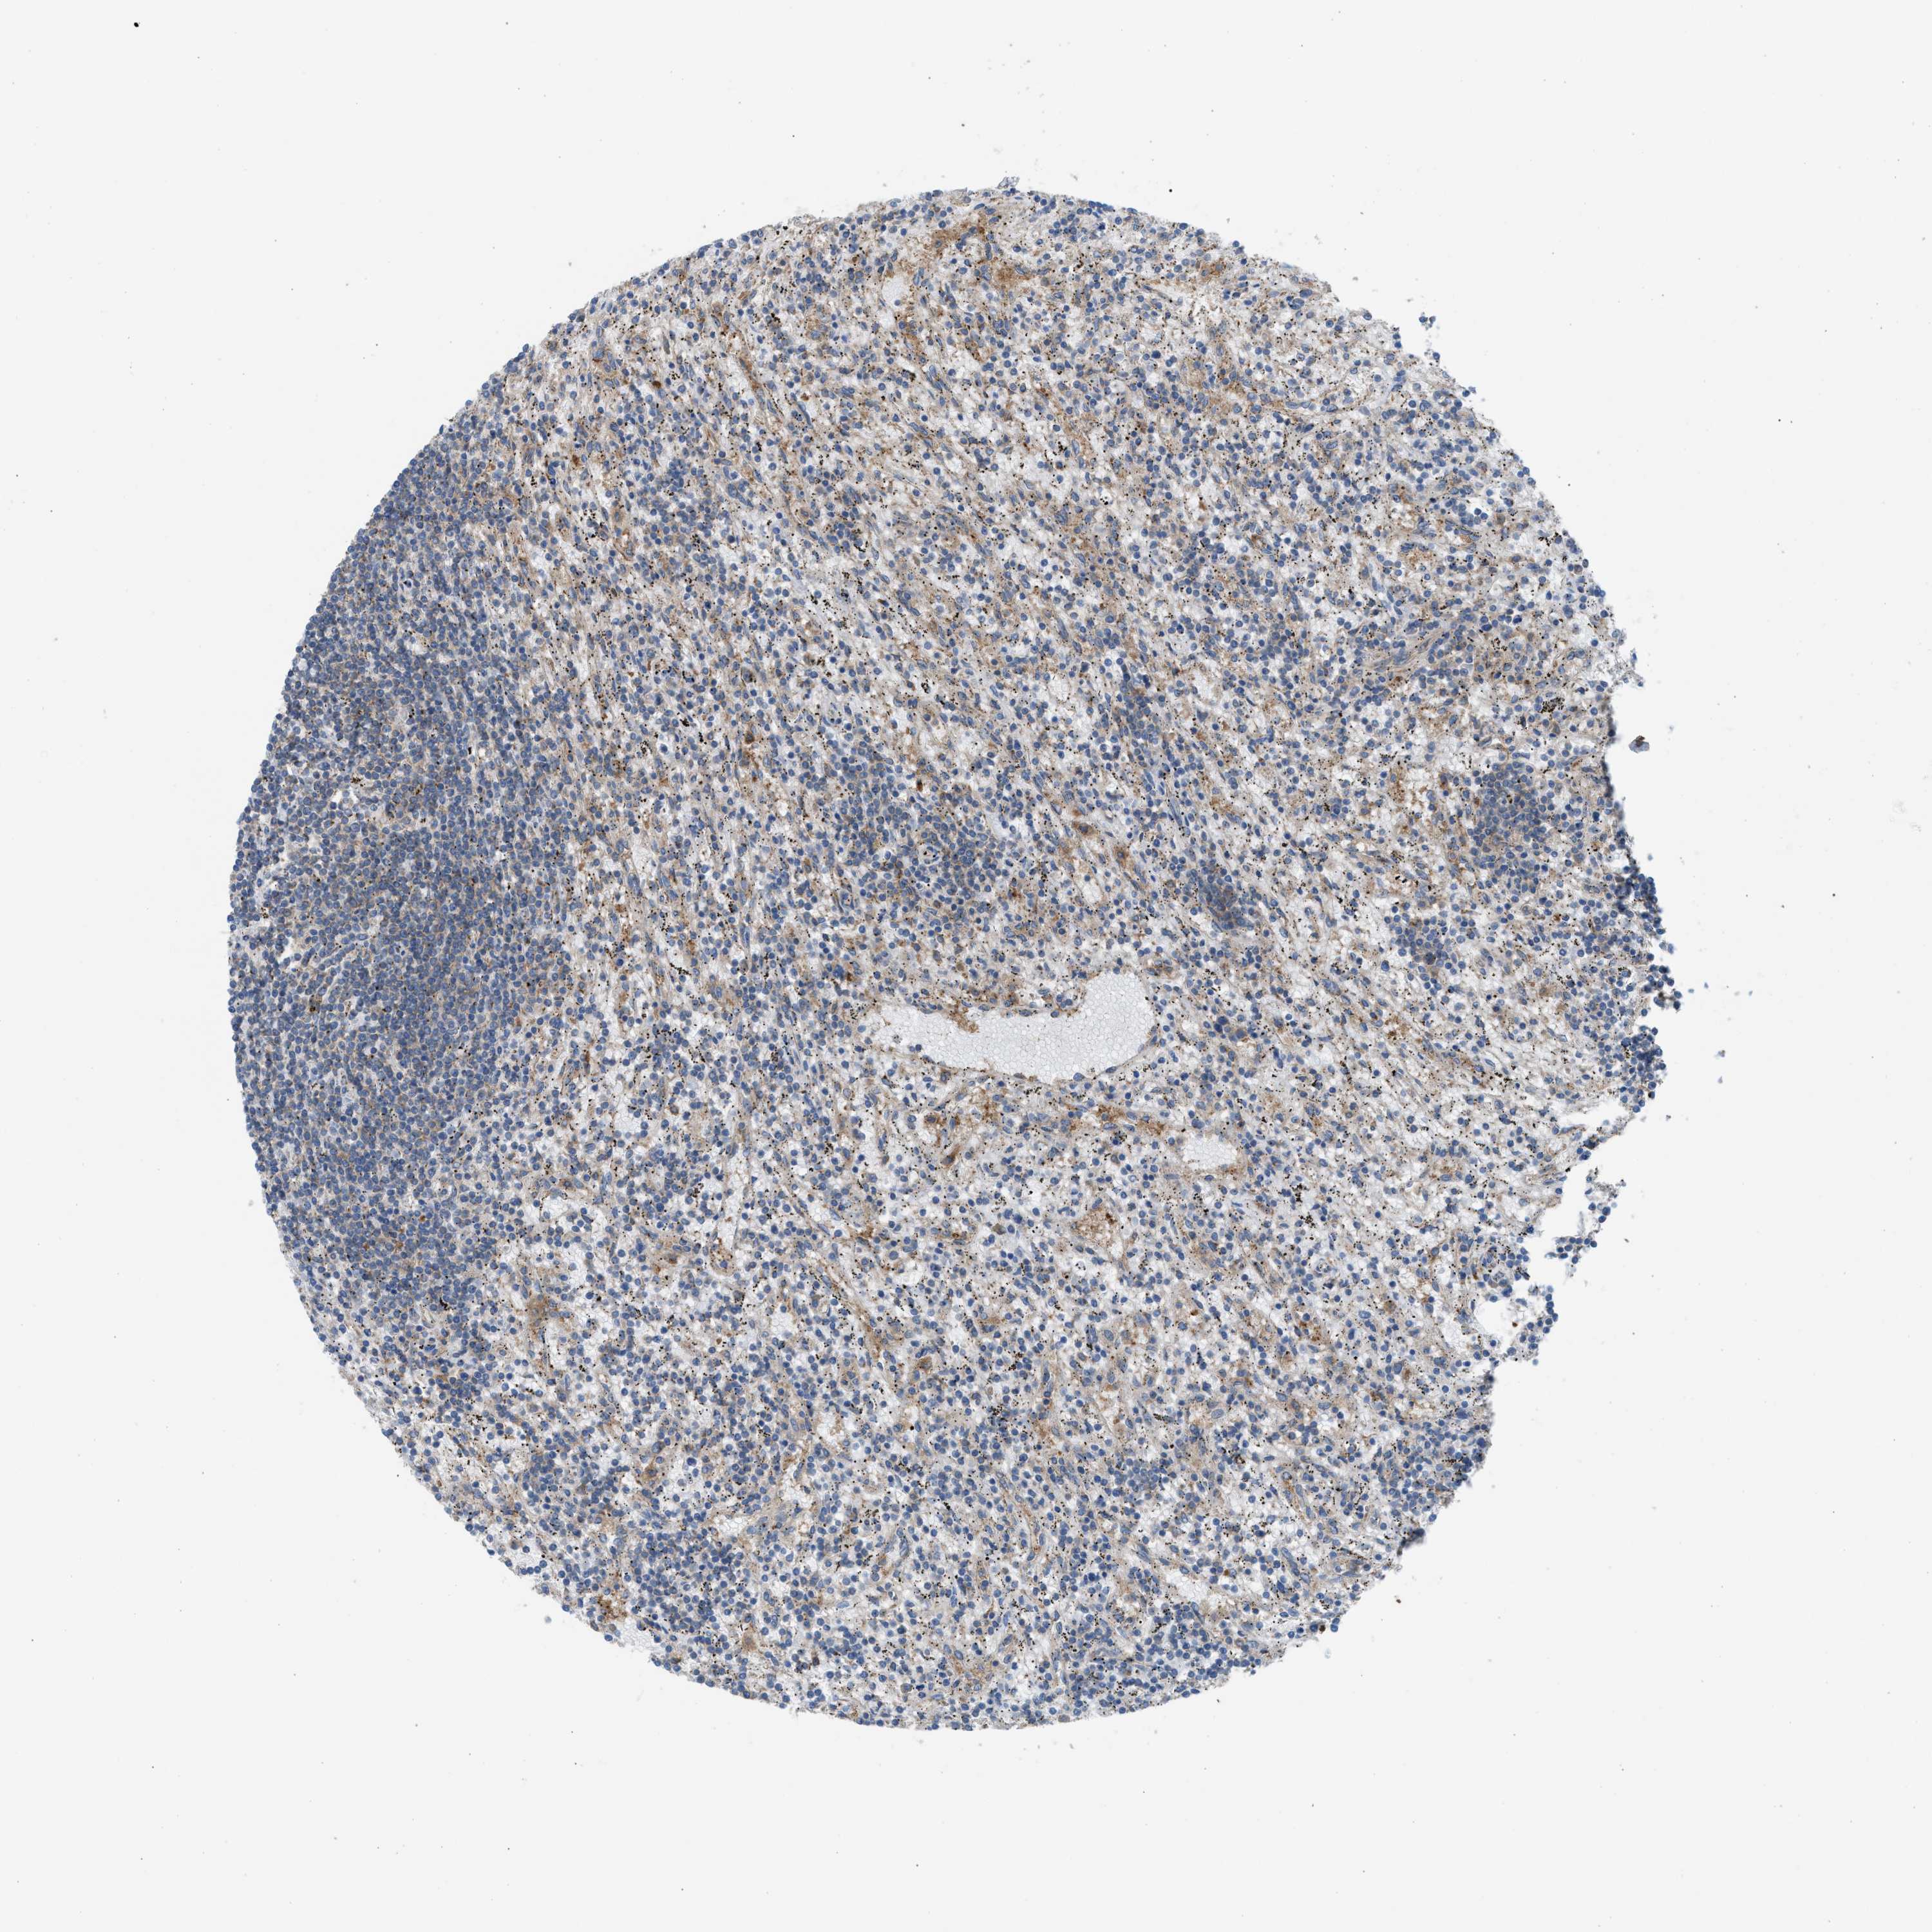

CANCER LYMPHOMA Show tissue menu

LYMPHOMA - Protein expressioni

A mouse-over function shows sample information and annotation data. Click on an image to view it in a full screen mode. Samples can be filtered based on level of antibody staining by selecting one or several of the following categories: high, medium, low and not detected. The assay and annotation is described here.

Each image is clickable and will lead to virtual microscopy that enables deeper exploration of all samples and also displays staining intensity scores, fraction scores and subcellular localization as well as patient and tissue information for each sample.

Antibody HPA021197

Staining

High

Medium

Low

Not detected

Intensity

Strong

Moderate

Weak

Negative

Quantity

>75%

75%-25%

<25%

None

Location

Nuclear

Cytoplasmic/membranous

Cytoplasmic/membranous,nuclear

Hodgkin's disease, NOS

Malignant lymphoma, non-Hodgkin's type, High grade

Malignant lymphoma, non-Hodgkin's type, Low grade